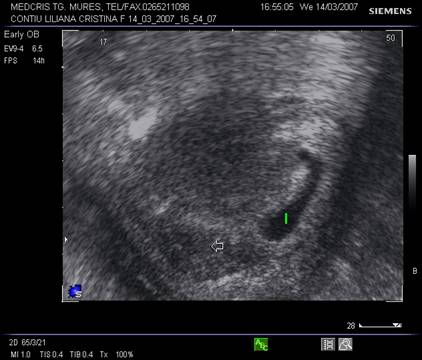

2. Avortul iminent

- Colul este dilatat evident ecografic si sacul gestational deformat este in partea de jos a cavitatii uterine.

Fig. nr. 79. Ou clar situat decliv ( cu sageata ) in avortul iminent